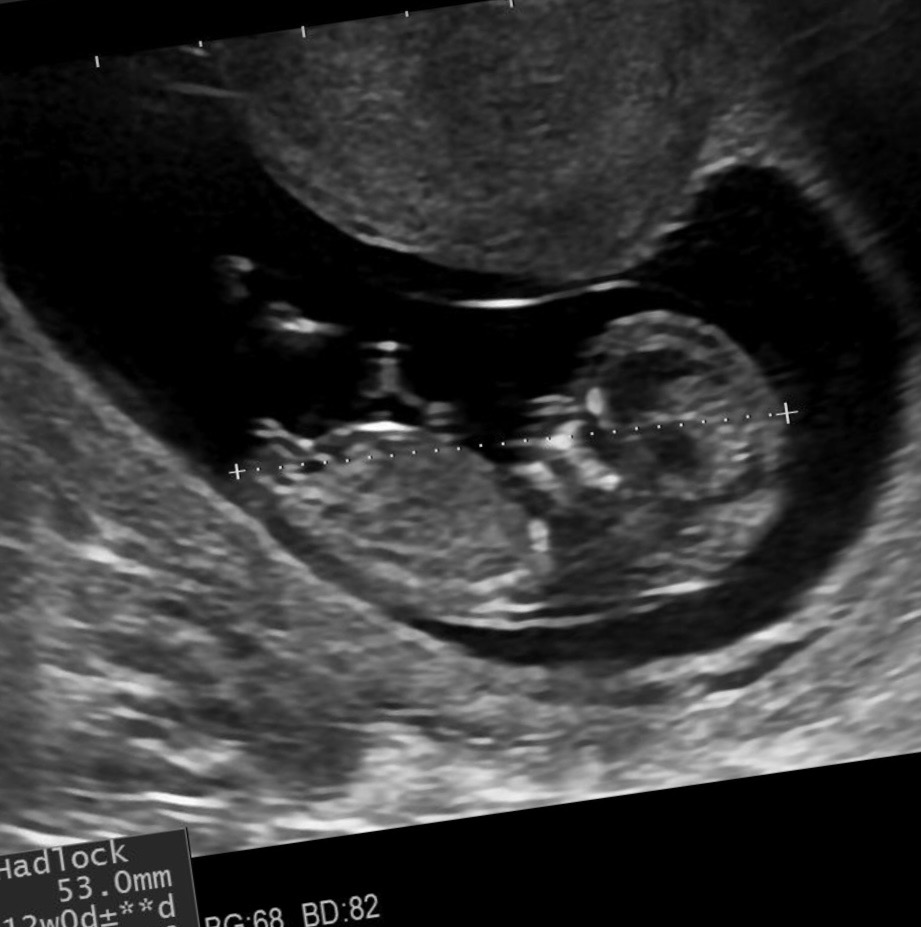

cinsel organı düz 80 derece aşağına bence kız

Kız iki çizgi var

Bence erkekkk